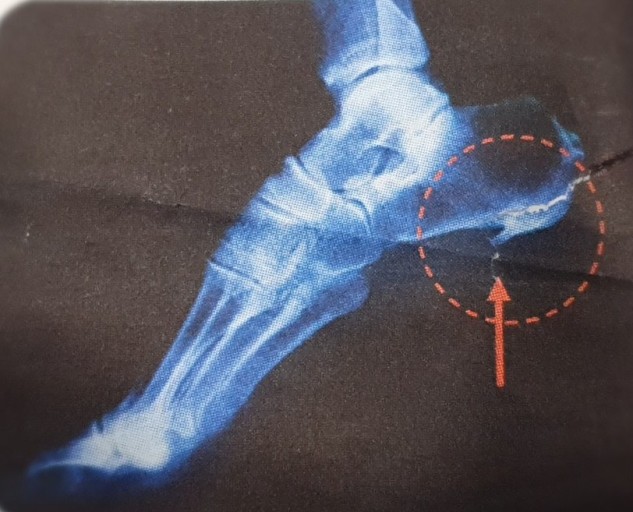

초기에는 밤에만 불편함을 느끼다가 점점 지속 시간도 늘어납니다.3. 족저근막염

발바닥 통증의 대표 질환으로,

발뒤꿈치에서 발바닥 전체로 이어지는 근막에 염증이 생기며

걷거나 서 있을 때 발바닥이 뜨겁고 찌릿한 통증을 유발합니다.

특히 아침에 첫 발을 디딜 때 더 아픈 경우가 많아요.